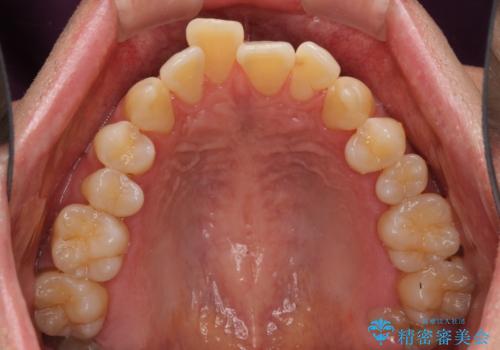

- 口元の閉じにくさと、前歯のでこぼこの歯並びを気にして来院された患者様です。

口元を積極的に引っ込めるために、上下左右の小臼歯計4本を抜歯することとしました。

叢生が強い場合、抜歯スペースが叢生を解消するために消費されるため、口元の突出感があまり改善されないことがあります。

今回の治療では、奥歯が前方に傾斜した歯並びだったため、奥に起き上がることで歯列が後方に移動し、横側からも口元が引っ込んだ感じが分かるほど改善されました。